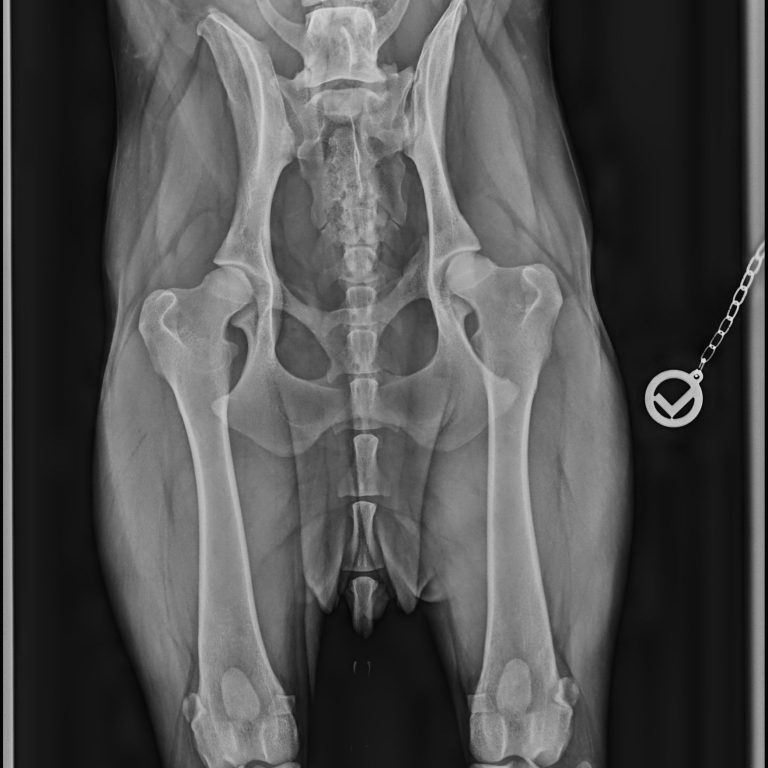

✔ nach Operationen (z. B. Kreuzband, Gelenke)

Sicher zurück in Bewegung – nach OP oder Verletzung

Nach einer Operation oder Verletzung braucht dein Hund gezielte Unterstützung, um wieder sicher und stabil in Bewegung zu kommen.